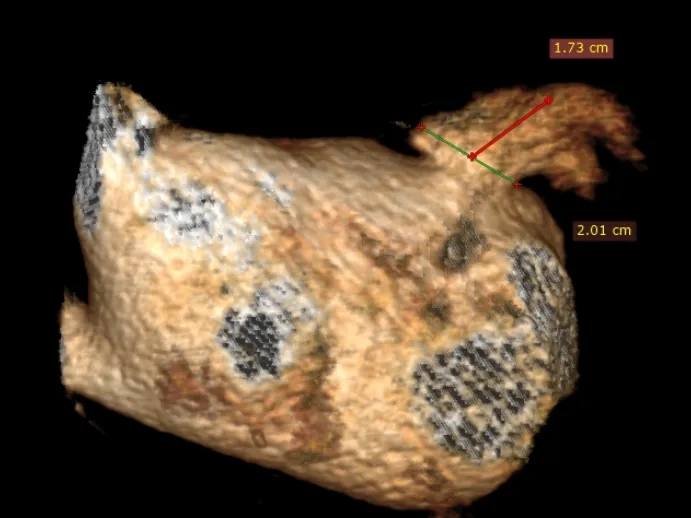

术前检查:心脏CT三维重建确认开口直径与心耳深度

RAO30度

CAU20度

左心耳大小20.1*17mm

CT三维平面左心耳开口形态及大小

左心耳开口近圆形,MPR周长66.4mm,化圆直径21.1mm,预选LAFDQ-23封堵器进行封堵

左心耳开口偏小,术前CT三维重建测量工作位左心耳大小20.1*17mm,正足位20度左心耳大小20.3*15.5mm,术中肝位造影确认左心耳大小为23.5*18.1mm。